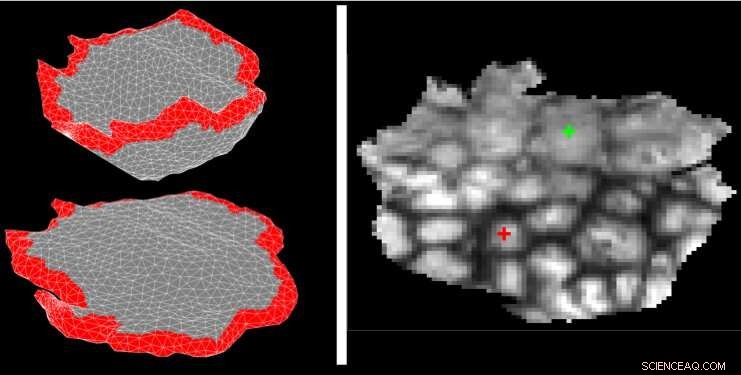

An algorithm developed at MIT takes MRI images of placentas (top) and flattens them to be more easily analyzed (middle and bottom). Credit: Massachusetts Institute of Technology

The team's algorithm first models the placenta's shape by subdividing it into thousands of tiny pyramids, or tetrahedra. This serves an efficient representation for computers to perform operations to manipulate the shape. The algorithm then arranges those pyramids into a template that resembles the flattened shape that a placenta holds once it's out of the body. (The algorithm does this by essentially moving the corners of the pyramids on the surface of the placenta to match the two parallel planes of the template and letting the rest fill the new shape.)

The model has to make a tradeoff between the pyramids matching the shape of the template and minimizing the amount of distortion. The team showed the system can ultimately achieve accuracy at the scale of less than one voxel (a 3-D pixel).